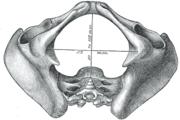

Additional images

Diameters of pelvic inlet.